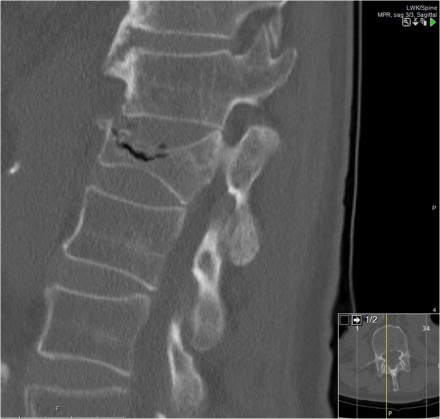

Here a fracture that just looks like another compression fracture on the lateral view.

At first glance the AP-view doesn't look very odd. That is until we zoom in and look at the distance between the spinous processes.

Now when you look carefully at the lateral view, you will notice that the facets are separated.

The MRI tells us the whole story.

You can see the edema related to the fracture of the vertebral body and the massive edema in the paraspinous muscles.

There is major disruption of the PLC of both the ligamenta flava and the interspinous ligament.

TLICS: distraction injury + PLC disruption.

This is an interesting case since non-surgical management was initially attempted in this patient.

However when we classify according to the TLICS-score, we give 4 points for the morphology and 3 points for the PLC.

Assuming the neurological exam was normal, this patient would still get 7 points.

Unfortunately, but not unexpectedly, conservative management failed with near-dislocation.

Finally a posterior spondylodesis was performed.